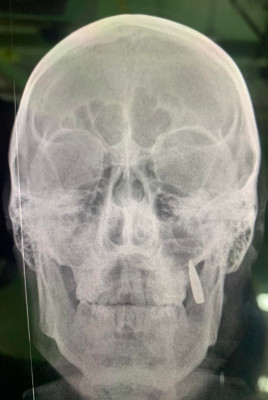

Do nemocnice přivezli 9 raněných ukrajinských vojáků. Lékaři ošetřují nejhorší případy. Jeden z raněných si chce jenom zakouřit a hned se zase vrátit zpět na pozice. Má malou ránu (ani nekrvácí) na tváři a něco mu vyrazilo dva zuby. Lékaři udělají pro jistotu rentgen. Místo dvou zubů je zapíchnutá kulka... Informovala o tom dobrovolnice Oksana Korchynska na svém Facebooku.